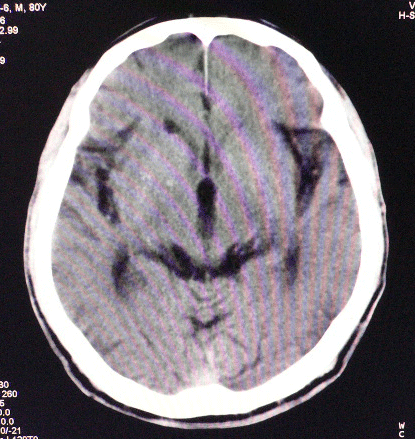

以下是引用狙击手在2007-4-8 22:45:00的发言:[br]出血?从患者的症状考虑病灶应该在左侧大脑半球的基底节区或颞顶部,如此小的病灶引起上述症状的可能性不大,患者可能有梗塞(时间短,目前ct还看不见)或是tia发作,再者像这样的线条形出血的确不多见,但还是有可能的,曾经碰到有外伤类似出血,复查后消失,所以还是慎重一点,短期复查即可。

以下是引用dyqct在2007-4-8 16:25:00的发言:[br]支持左侧放射冠区少量出血。